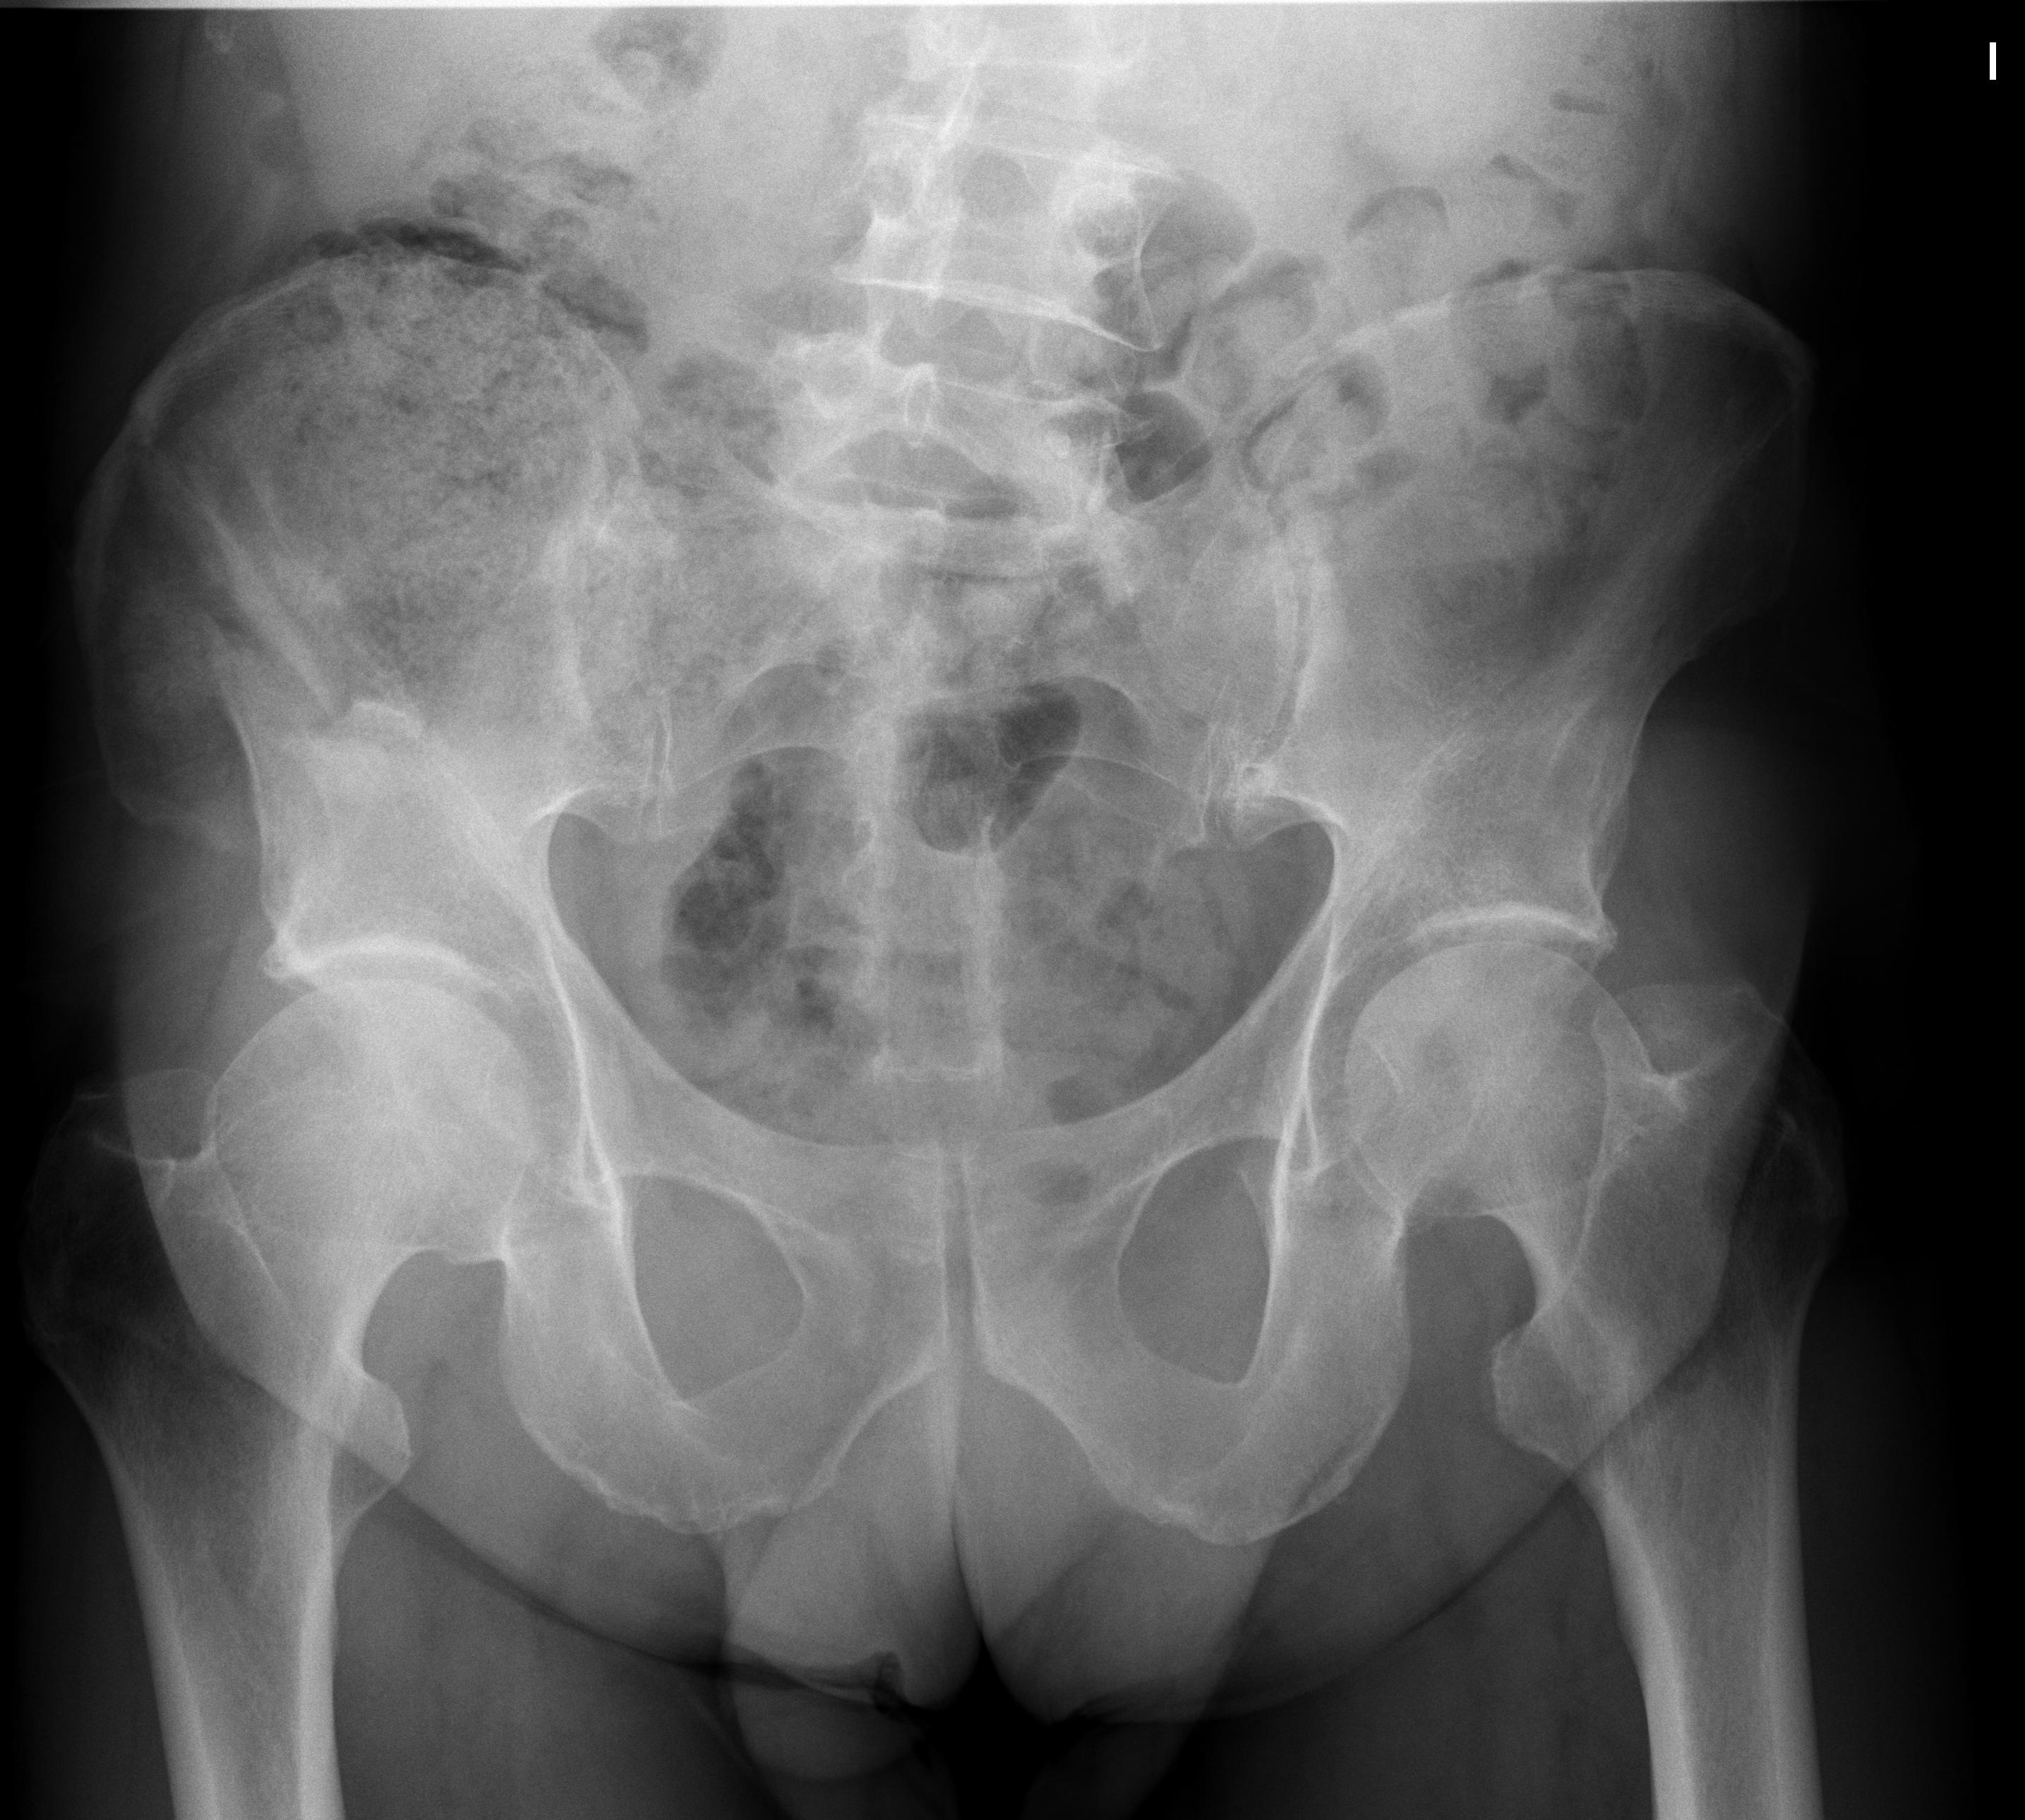

1 Pelvis